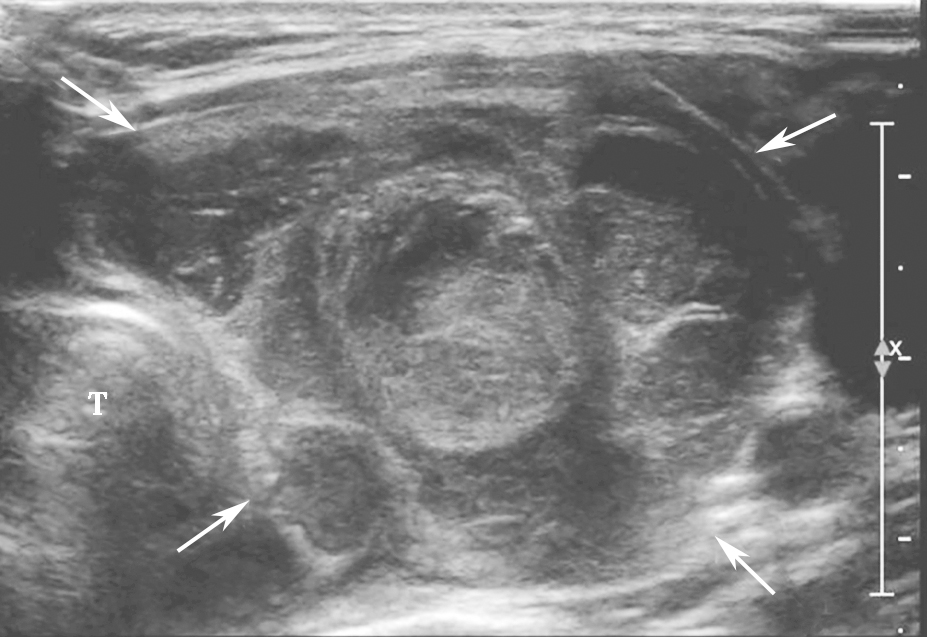

甲状腺滤泡癌和滤泡腺瘤在超声上鉴别有一定困难,即使是FNA细胞学也很难鉴别。但有报道认为:与甲状腺乳头状癌不同,甲状腺滤泡癌常为等回声或高回声,微小钙化很少见,病变多伴有厚薄不一的低回声晕或者局部低回声晕。彩色多普勒血流信号丰富也是该类病变的特点之一(图11、图12)。

:内部回声不均伴厚薄不一低回声晕.jpg)

图11右侧颈部纵切面:甲状腺右叶中部中等回声(箭头所示):内部回声不均伴厚薄不一低回声晕

:中等回声彩色多普勒血流信号丰富而杂乱.jpg)

图12右侧颈部纵切面(与图3-3-11同患者、同切面):中等回声彩色多普勒血流信号丰富而杂乱